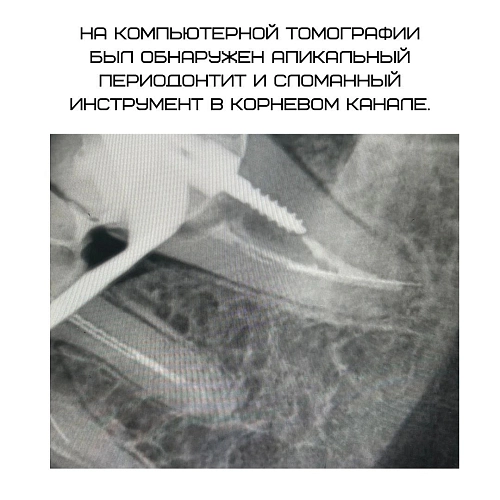

сломанные инструменты в каналах.

На фото работа Гордеевой Людмилы Валерьевны